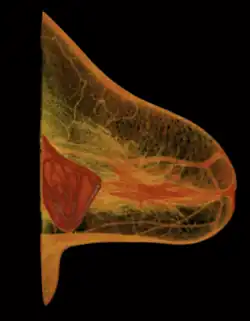

A breast implant is a prosthesis used to change the size, shape, and contour of a person's breast. In reconstructive plastic surgery, breast implants can be placed to restore a natural looking breast following a mastectomy, to correct congenital defects and deformities of the chest wall or, cosmetically, to enlarge the appearance of the breast through breast augmentation surgery.

In surgical practice, for the reconstruction of a breast, the tissue expander device is a temporary breast prosthesis used to form and establish an implant pocket for the future permanent breast implant. For the correction of male breast defects and deformities, the pectoral implant is the breast prosthesis used for the reconstruction and the aesthetic repair of a man's chest wall (see: gynecomastia and mastopexy).

- Prepectoral or subcutaneous: in a breast reconstruction following a skin-sparing or skin- and nipple-sparing mastectomy, the implant is placed above the pectoralis major muscle without dissecting it so that the implant fills directly the volume of the mammary gland that has been removed. To avoid the issue of capsular contracture, the implant is often covered frontally or completely with a mesh in biomaterial, either biological or synthetic.